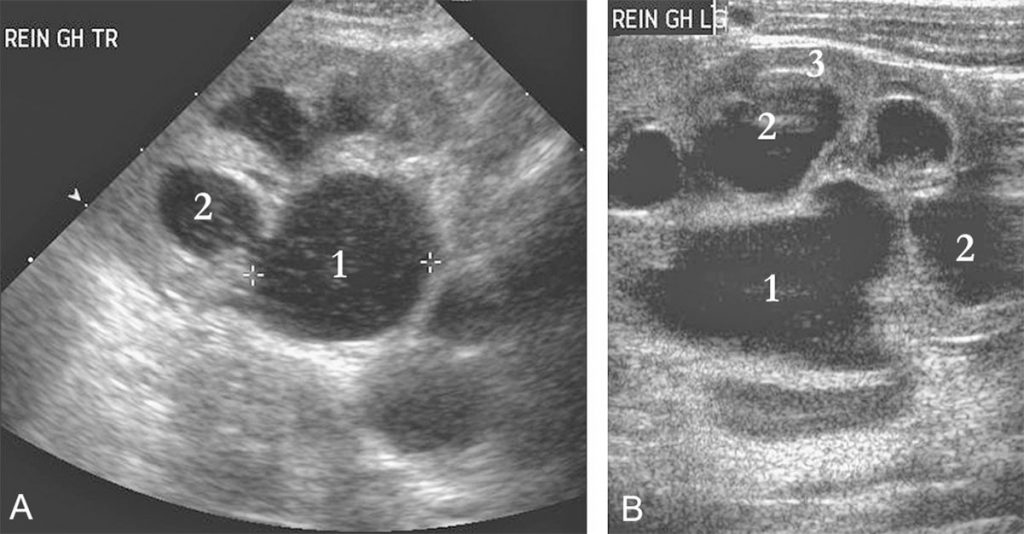

- l’échographie de l’appareil urinaire (figure 108.1) ;

Fig. 108.1. Échographie du rein gauche : coupes transversale (A) et longitudinale (B).

L’échographie montre une dilatation du pelvis rénal (1) associée à une dilatation des calices (2) communiquant avec le bassinet. Il existe une réduction de l’index parenchymateux en regard (3). La coupe réalisée au niveau pelvien ne montrait pas de dilatation du bas uretère.

Source : CERF, CNEBMN, 2022.